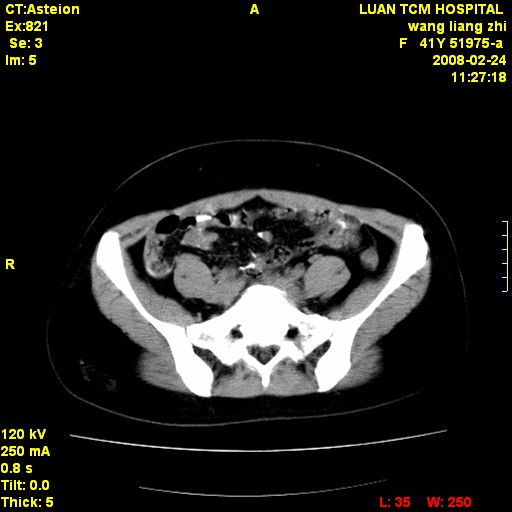

以下是引用dyqct在2009-8-23 16:17:00的发言:[br]考虑:1、造影剂进入腹腔、结肠旁沟、肝周;[br] 2、子宫明显增大(腺肌增生症?);[br] 3、膀胱显影是由于造影剂吸收后经肾分泌进入膀胱的;[br] 4、建议mri检查子宫。